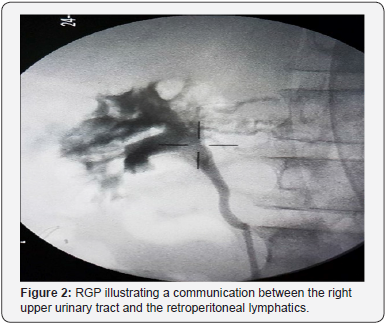

A 77-years-old patient from Martinique who has a history of gastric ulcer with a left inguinal hernia, admitted to our formation for the management of chronic chyluria complicated by acute urinary retention. Urine cytology was inflammatory with a negative parasitic assessment. Uroscan was normal. The cystoscopy showed very turbid urine without being able to specify the side reached. Complement with RGP revealed multiple anastomoses between the lymphatics of the left kidney and the urinary tract (Figure 1A). We opted for a transperitoneal laparoscopic with left-lymphatic disconnection. The evolution was marked by a recurrence of chyluria 6 months later. A new cystoscopy and RGP revealed a good surgical result for the left side Figure 1B with appearance of communication between the right upper urinary tract and the retroperitoneal lymphatics (Figure 2). We proceeded in the same way for the right side as the left side (a transperitoneal laparoscopic reno-lymphatic disconnection) with good clinical evolution.